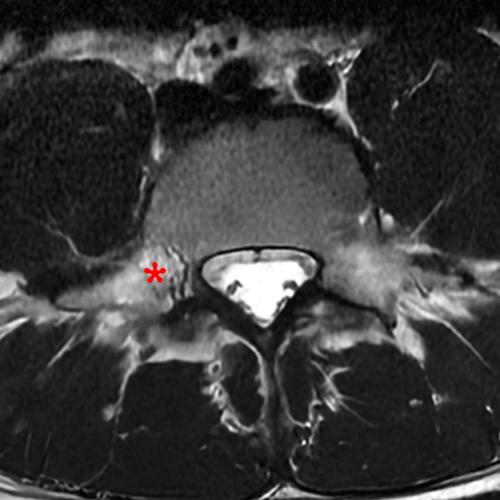

Case 2: 19-year-old male baseball player with acute onset of back pain after hitting a ball. Axial T1-weighted (2A) and T2-weighted (2B) images are provided. What are the findings? What is your diagnosis?

Case 2: T1-weighted (4A) and T2-weighted (4B) axial images show T1 hypointensity and T2 hyperintensity (arrowheads) in the left lamina of L5 adjacent to a small hypointense line (arrows) which traverses the lamina.

Case 2: Acute left-sided laminolysis